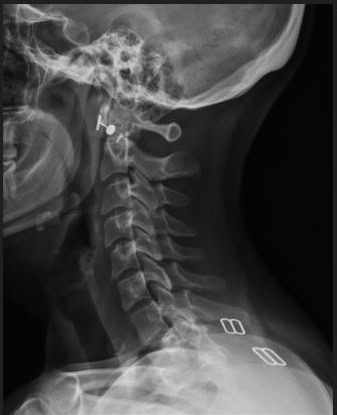

Pre Scan